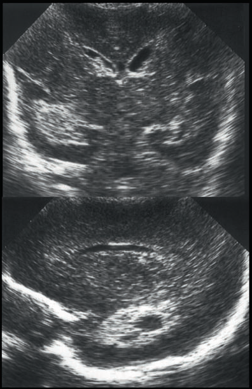

Neonatology PVHI Thalamus 3 Image